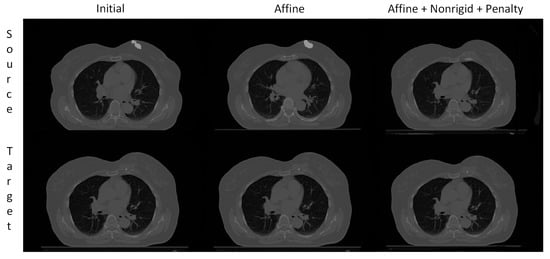

3.3. Visual Assessment